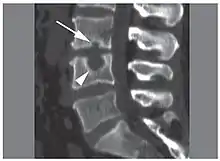

| X-ray image of Schmorl's nodes in the lumbar spine | |

Schmorl's nodes can be detected with X-rays, although they can be imaged better by CT or MRI. They are considered to be vertical disc herniations through the cartilaginous vertebral body endplates. Schmorl's nodes can sometimes be seen radiographically, however they are more often seen on MRI, even when not visible on plain X-rays. They may or may not be symptomatic, and their etiological significance for back pain is controversial. In a study in Spine by Hamanishi, et al., Schmorl's nodes were observed on MRI in 19% of 400 patients with back pain, and in only 9% of an asymptomatic control group. The authors concluded that Schmorl's nodes are areas of "vertical disc herniation" through areas of weakness in the endplate.[4]